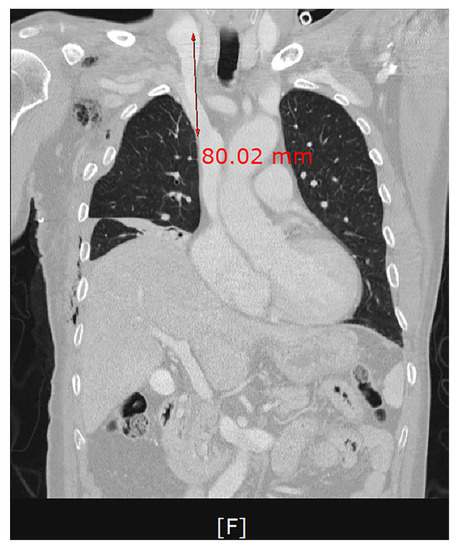

After the insertion of a trocar in the fifth intercostal space on the midaxillary line and that of a thoracoscope, we noticed that bleeding and hematoma occurred in the SVC. The site of perforation was located in the extra-pericardial portion of the SVC.Even after the aspiration of blood at a volume of approximately 700 mL, bleeding was persistently present at the site of perforation in the SVC. This was accompanied by the presence of hematoma in the right brachiocephalic vein (Figure 1). The patient had a gradual decrease in blood pressure. Therefore, the patient received a continuous intravenous infusion of norepinephrine 0.05 μg/kg/min and the crystalloid solution at a rate of 600 mL/hr. For hemostasis, the site of bleeding in the SVC was compressed using a gauze pad for 20 min, followed by the use of an active absorbable collagen hemostat. On noticing that bleeding was discontinued, we performed surgery to remove foreign bodies from the esophagus (Figure 2).

Figure 3. A frontal computed tomography scan of the chest. Approximately 80% of the length of a dilator corresponding to the distance between the site of puncture on the internal jugular vein and that on the superior vena cava.

We assumed that a dilator caused an injury to the wall of the SVC while being pushed deeply at the point of a crooked part in the first session of the CVC. We used a dilator with a length of 10.2 cm. Approximately 80% of the length of a dilator corresponded to the distance between the site of puncture on the internal jugular vein and that on the SVC (Figure 3). This is in agreement with a previous report that it would not be necessary to insert a dilator of ≥8 cm in length [22].